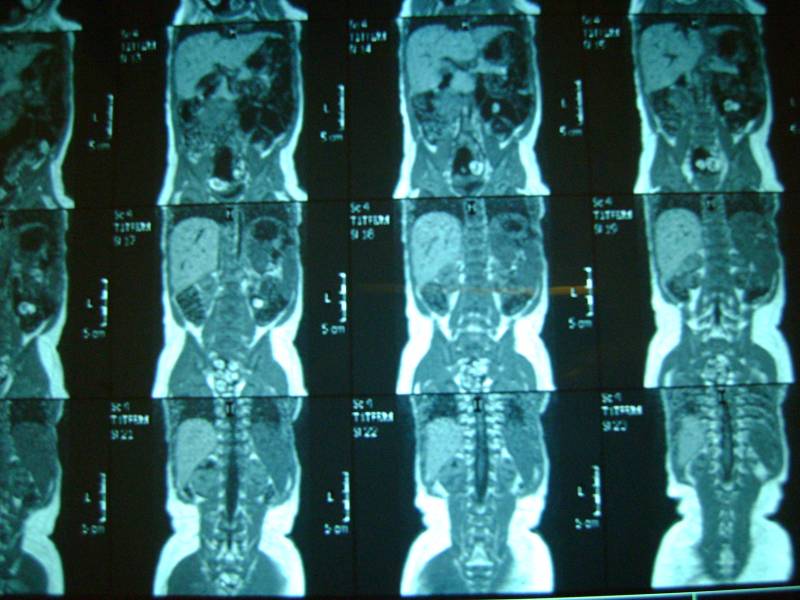

Уважаемый доктор просим посмотреть снимки и нашего сына! Возраст 10 мес. два близнеца однояйцевых у одного поликистоз у второго нет. Можно ли понять тип поликистоза детский или взрослый? Можно ли отправить диск со снимками мрт Вам если можно то куда? К генетикам пойдем в ближайшую среду. Заранее огромное спасибо!!! Попробуем еще фото выложить

Добавляем еще фото